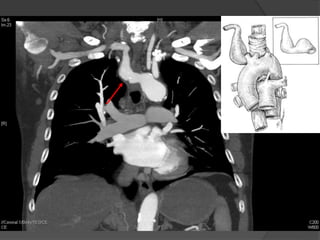

Cas 1

 Reparation par stages (3) et trois admissions.

 Stage 1: transposition carotido-sousclavien

gauche

 Stage 2: Pontage carotido-sousclavien droit

(Gore Tex)

 Stage 3: TEVAR (Zenith TX2)

- transfemoral

- pacemaker transveneux ventriculaire

durant placement du stent thoracique

Suites Post-operatoires: CTA

 Aucunes

endofuites ou

migration

 Exclusion

complete et

thrombose de

artere lusorienne

ainsi que le

diverticule